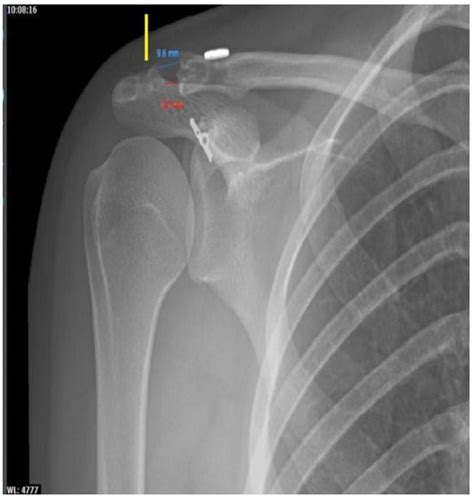

Acromioclavicular Joint X Ray